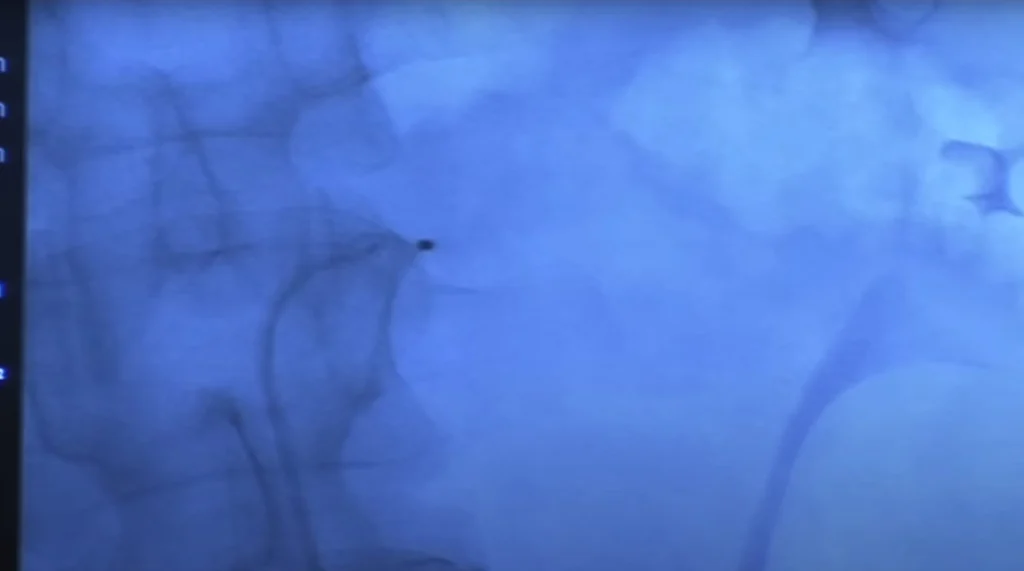

La procedura consiste nell’inserimento di un catetere del tutto simile a quello utilizzato per la

vascolarizzazione cardiaca che viene fatto avanzare fino alle arterie renali. Una volta

posizionato, il catetere lancia un segnale in radiofrequenza, in grado di distruggere le fibre

nervose dell’arteria del sistema simpatico renale e inibirne quindi l’attività consentendo una

riduzione significativa dei valori pressori.